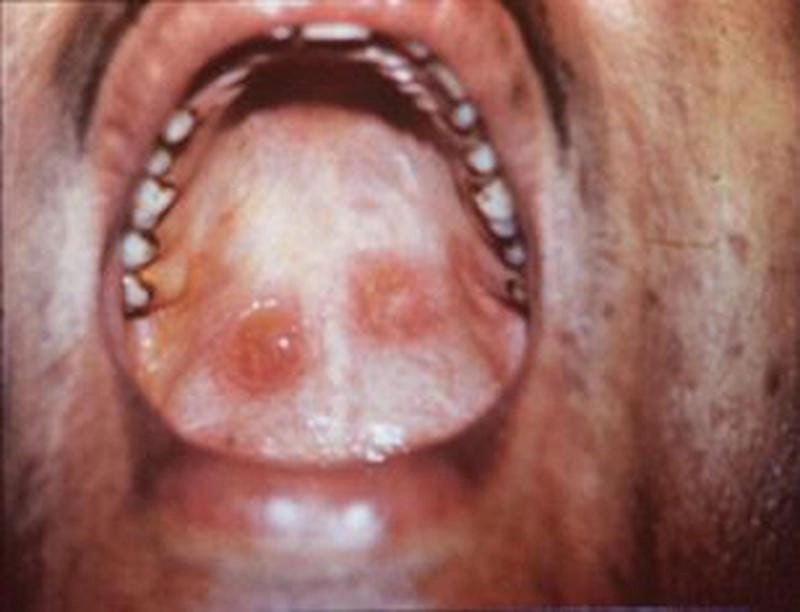

Nhiều người vẫn mơ hồ không biết hình ảnh bệnh giang mai là như thế nào, và đó chính là lý do họ dễ lơ là cảnh báo đầu tiên. Những vết trợt nông không đau, không ngứa, tưởng chừng vô hại nhưng lại chính là “báo hiệu đỏ” cho một chuỗi biến chứng nguy hiểm. Dưới lớp da tưởng như lành lặn kia có thể là ổ chứa xoắn khuẩn giang mai đang âm thầm tấn công hệ thần kinh, tim mạch.

Nếu bạn nghĩ giang mai là căn bệnh đã “xưa như trái đất” thì hãy xem ngay tổng hợp ảnh giang mai mới nhất 2025. Những hình ảnh cận cảnh, rõ nét từng giai đoạn từ sơ cấp, thứ cấp cho đến tiềm ẩn và cuối cùng là giang mai thần kinh sẽ khiến bạn “rùng mình”. Đây không chỉ là tài liệu y khoa mà còn là lời cảnh báo nghiêm túc cho những ai đang sống buông thả và thiếu kiến thức phòng bệnh.